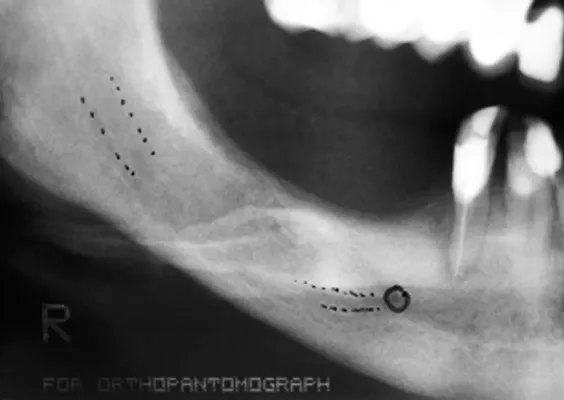

TRANSPOZYCJA NERWÓW ZĘBODOŁOWYCH DOLNYCH – IANT

Ta szczególna metoda używana jest w obszarze dolnego łuku zębowego w sytuacji braku dostatecznej ilości kości na wysokość. Metoda stosowana jest w sytuacji rozległych zaników kostnych w bocznych odcinkach żuchwy, w której wprowadzenie implantów groziłoby uszkodzeniem gałązek nerwowych nerwów zębodołowych dolnych. Gałązki nerwowe biegną wraz z naczyniami krwionoś-nymi we wspólnej pochewce w kanałach kostnych, umieszczonych symetrycznie po obu stronach w trzonach żuchwy.

Technika polega na chirurgicznym ich przemieszczeniu, a przez to stworzeniu bezpiecznego miejsca dla wszczepienia implantów o odpowiednej długości, co gwarantuje ich stabilną pozycję. Stosuje się ją wraz z zabiegiem rekonstrukcji kostnej przy użyciu biomateriałów w formie granulatu i membran.

Zabieg ten stosowany jest rzadko, jako alternatywa rozległych regeneracji kostnych. Wybierany bywa jako alternatywa operacyjna tylko w sytuacji, gdy konwencjonalne metody odbudowy kostnej są niewystarczające lub generują ryzyko braku skutecznej odbudowy kostnej celem wszczepienia implantu.